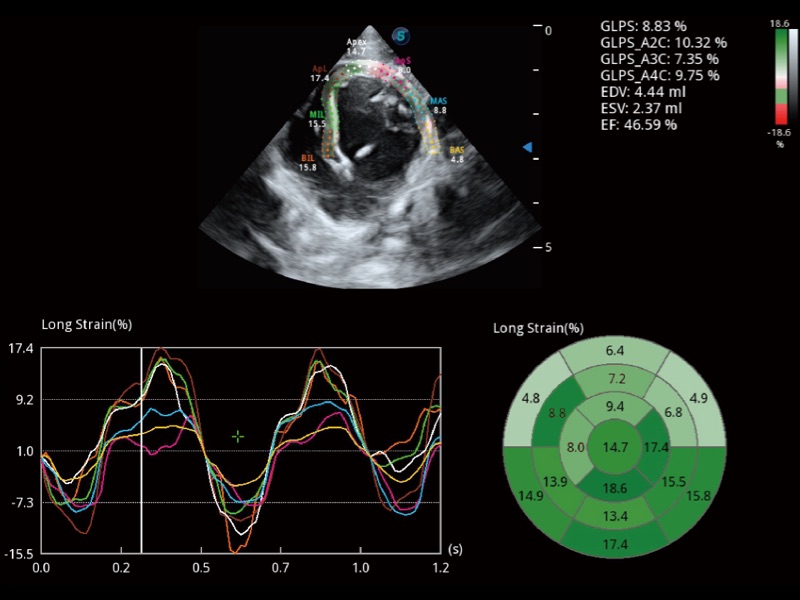

能够基于左心室壁追踪和辛普森法,自动计算射血分数,支持多个可移动点描迹,与手动测量相比,极大节省了动物医生的时间和精力。

具备多种协议可选,同时支持17阶段划分法和专业的SE报告。

通过360度任意调节3条M型取样线,在同一心动周期上观察心脏不同位置的运动曲线,得到准确的心功能测量数据,有效评估心肌运动及左心室功能。

实时用颜色表示心肌组织运动,观察和定量组织的运动情况,对快速检测与评估心肌的灌注和活性、电传导及心肌收缩和舒张功能等均能提供重要的诊断信息。

当心脏测量结果超出正常范围时,可实时预警提示动物医生,减少疾病漏诊概率。